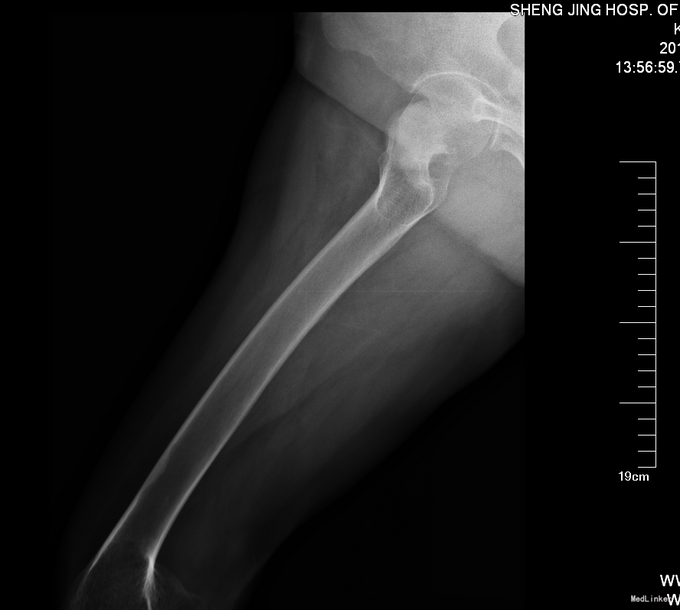

主诉:摔伤后右髋部疼痛活动受限9小时 现病史:患者及家属自述患者于2014年4月24日在中国医科大学附属盛京医院门口被人推倒摔伤,致右下肢疼痛活动受限。被急送至我院急诊就诊。行骨盆DR,右下肢DR检查示:右股骨颈骨折。患者为求系统诊治来我科治疗。患者平车入病房,无发热,无头晕头迷,无胸闷气短,无心慌心悸,无腹痛腹胀,受伤后大便未排,小便正常。

查体右髋部未见明显肿胀及瘀斑,右大腿外旋畸形约45度。右股动脉搏动有力,肢体末梢血运良好,皮温正常。右髋部压痛(+)扣击痛(+)。右髋关节活动受限。